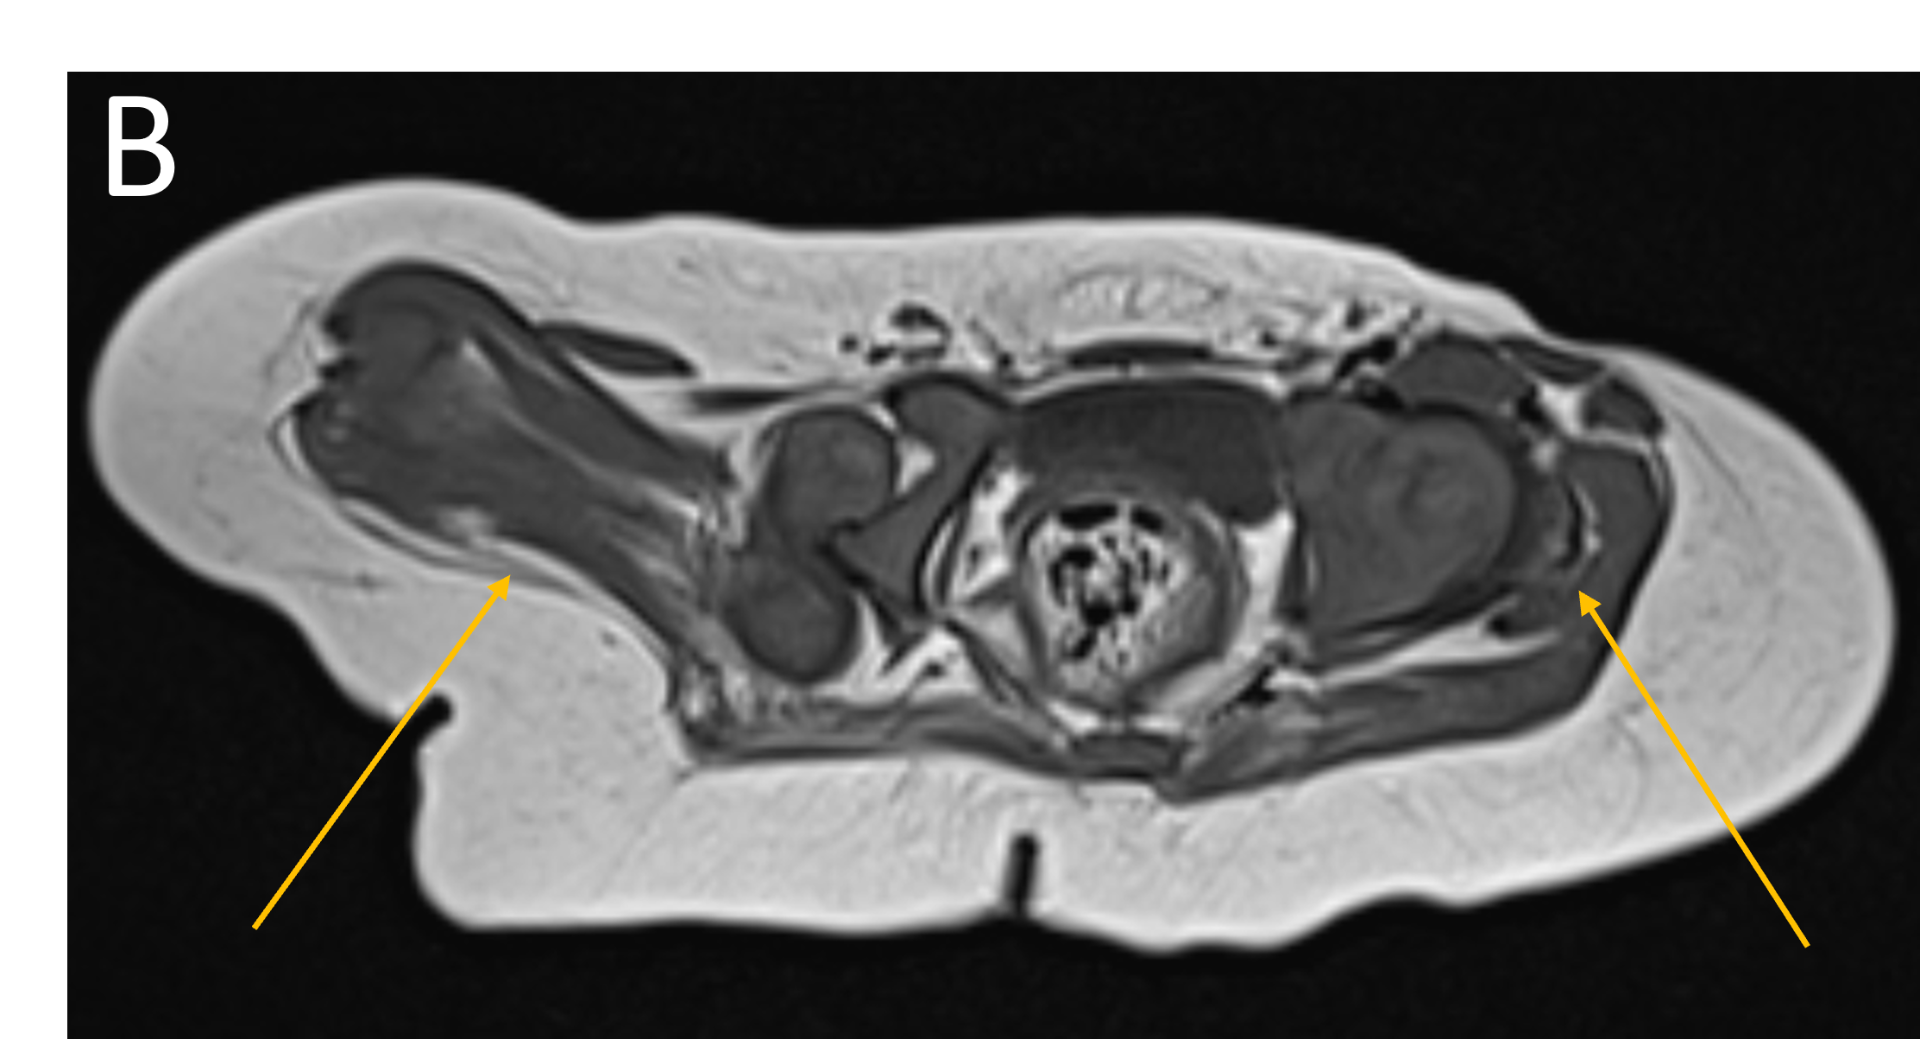

- B.LEGENDS – MR BILATERAL HIPS : Generalised atrophy of muscles of thigh and gluteal region on the right compared to the left.

Bilateral Proximal focal femoral deficiency (class B on right side and class C on left side).